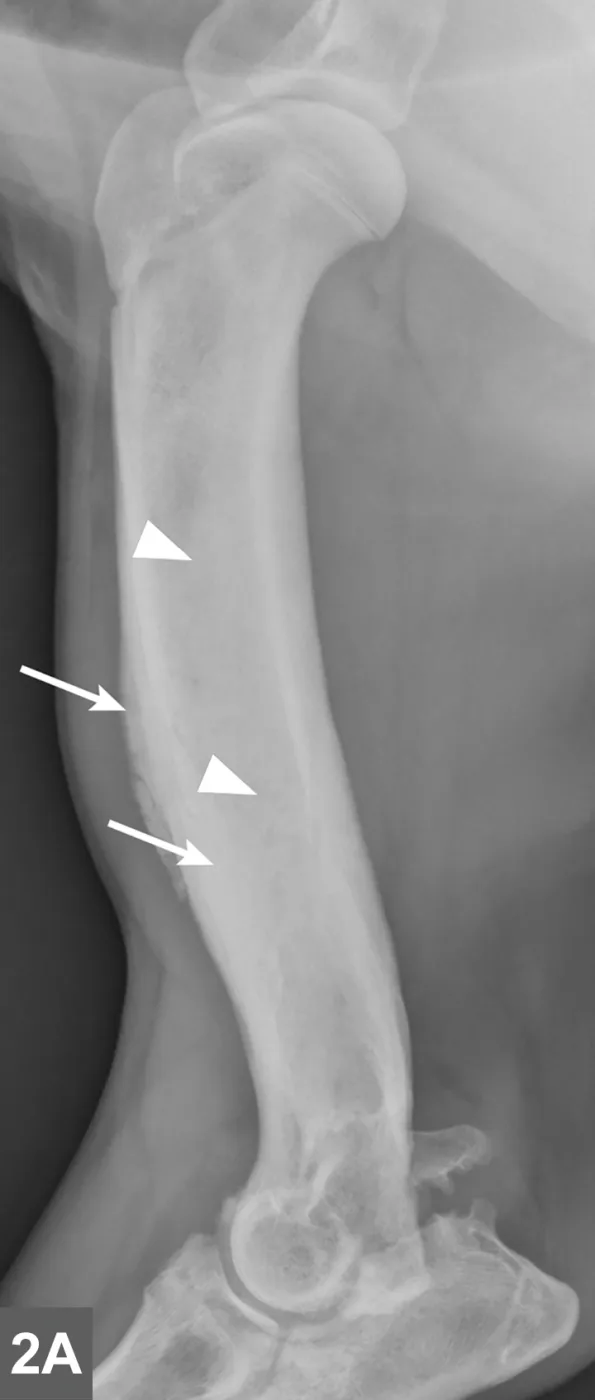

Radiographic signs of panosteitis frequently lag days to weeks behind clinical signs.1,3 The earliest radiographic sign of panosteitis is a decrease in opacity around the nutrient foramen. Later signs include an increase in mineral opacity within the medullary canal of long bones and loss of the normal trabecular bone pattern (Figure 1). Smooth periosteal and endosteal new bone may also be seen in more severe cases (Figure 2). Radiographs of the affected limb may be compared with those of the contralateral limb to assist in diagnosis. Nuclear scintigraphy may assist in diagnosis in cases in which radiographic changes have not yet developed.4

Lateral radiographic projections of the femur (A) and ulna (B, next slide) in dogs with early signs of panosteitis. Note the radiolucency around the nutrient foramen (arrows) and increased opacity within the medullary canal (arrowheads) in both cases.